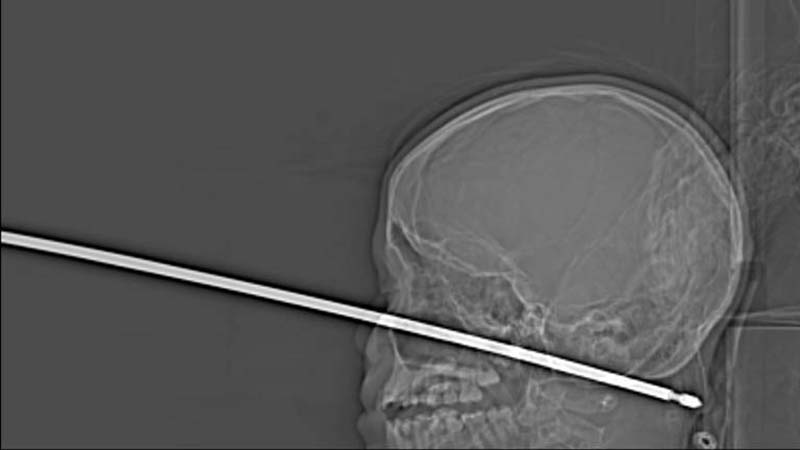

Всё произошло, когда паренёк игрался в домике на дереве, именно тогда-то на него и напали осы, которые и привели к тому, что он совершил падение с более чем метровой высоты прямо на шампур для приготовления шашлыков. Острый штырь пронзил череп мальчика, погрузившись в ткани головы на 15 сантиметров. К счастью, чудесным образом металлическая палка вошла в голову, миновав и глаза, и мозг, и спинной мозг, и крупные кровеносные сосуды.

Врачи успешно удалили квадратный стержень, так как из раны не было активного кровотечения и шампур не повредил жизненно важные органы. Сама операция была довольно непростой, в основном из-за формы шампура, который имел острые края, поэтому врачам пришлось провозиться с извлечением предмета несколько часов.

Директор отделения эндоваскулярной нейрохирургии больницы Университета Канзаса Коджи Эберсоул (Koji Ebersole) сказал, что самую большую сложность для хирургов при удалении шампура представляли кровеносные сосуды на шее паренька. Врач назвал чудом то, чтобы при такой сквозной травме шампур не повредил ничего в голове потерпевшего роковым образом.

Доктор добавил, что ему никогда ранее не приходилось видеть, чтобы так глубоко проникший в голову предмет не нанёс бы травмы, не совместимые с жизнью. И уж тем более чудом он считает, что восстановление раненого мальчика будет или полным, или почти полным.